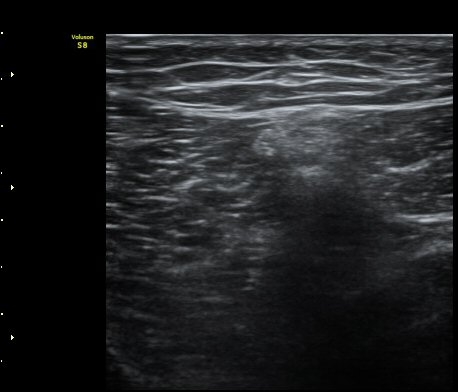

º¹Àç½Å°æ ½½°³°ñÇϰ¡Áö°¡ È®ÀÎµÈ »óÅ¿¡¼­ ´ëÅð ¾Õ¿¡¼­ ÃÊÀ½ÆÄÀ¯µµÇÏ ½½°³°ñÇϰ¡Áö

Â÷´ÜÀ» ½ÃÇàÇÏ¿´´Ù(÷ºÎ ÆÄÀÏ 2).

saphenous nerve block with triamcinolone 20mg +1% lidocane 4cc

¹«¸­ÀÇ ½ÉÇÑ ÅëÁõ ½Ã º¹Àç½Å°æÀÇ ½½°³°ñÇϰ¡Áö¸¦ ¼±ÅÃÀûÀ¸·Î Â÷´ÜÇϸé

¾Æ·§´Ù¸®ÀÇ °¨°¢ÀúÇÏ µî ºÒÇÊ¿äÇÑ ÇÕº´Áõ ¾øÀÌ ¹«¸­ ÅëÁõ °ü¸®°¡ °¡´ÉÇÏ´Ù.